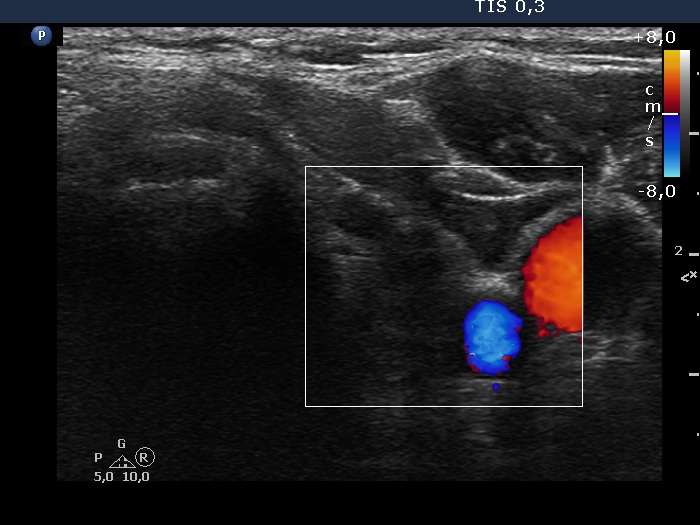

Right lobe, longitudinal scan

Left lobe, transverse view, color Doppler mode. The lobe is avascular on Doppler mode.